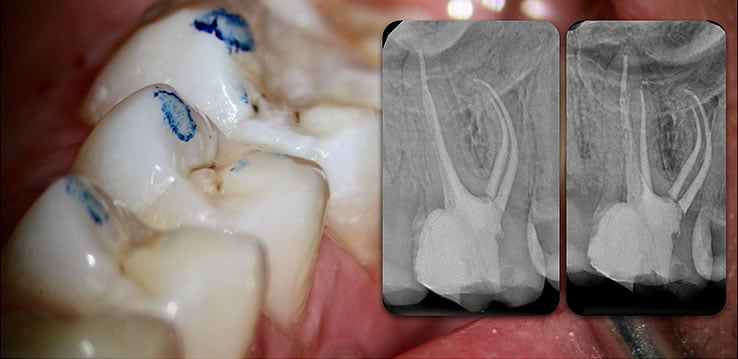

Retain 100% of remaining healthy tooth structure

- Biolight® DRILL-FREE adapts to all shaped canals, while conserving all remaining healthy tooth structure.

- There is no need to drill out portions of canals to accommodate post spaces.

- Easily place multi-posts in multiple canals as the post bends with the natural canal shape.